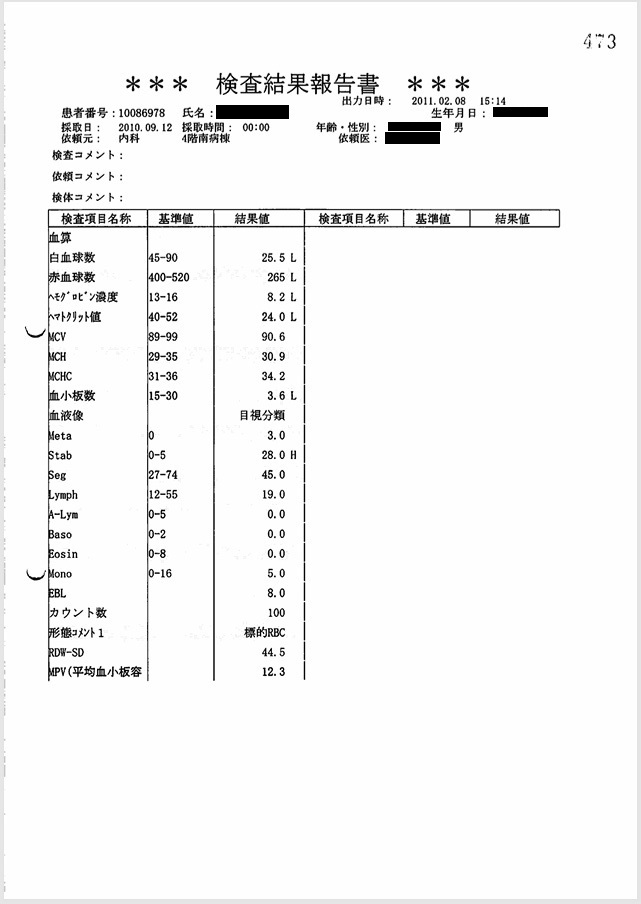

- 9月12日:出血傾向はごく軽度

PT-INR 1.3, APTT 35 sec, 血小板3.6万/μl, Hb 8.2 g/dl:出血傾向はごく軽度で硬膜下血腫の自然発生は否定的。この時、父は意識がなく自ら動くことはできない状態であったため、頭部を殴打された可能性しか残らない。

証拠:血液検査データ(9月12日)

この時、撮影された頭部CTで急性硬膜下血腫が認められた。これが父の直接の死因となった。 医師からもその説明があったが、 直接の原因と推定される「頭部打撲」には一切言及がなく(録音記録あり)、 DIC(播種性血管内凝固)に伴う出血傾向による自然出血とのことだった。 しかしほぼ同時に行われた血液検査では、「PT-INR 1.3, APTT 35 sec, 血小板3.6万/μl」と 出血傾向はごく軽度であり、自然発生的に頭蓋内に出血を起こす可能性は皆無と言ってよい。